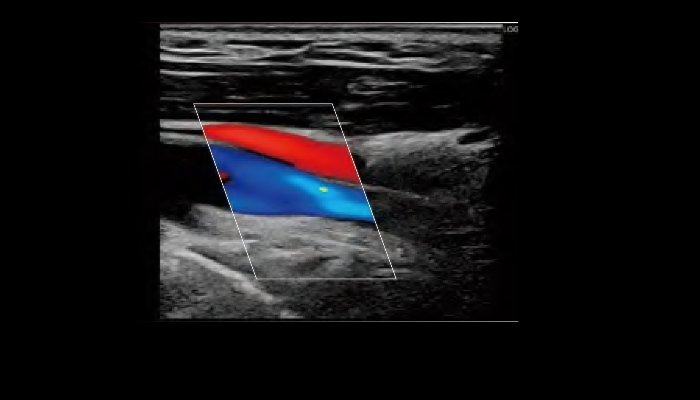

エコー検査装置 エコー検査装置GE社製エコー検査装置 心臓エコー 心臓心臓の動きや心臓弁膜症を調べます。 乳腺エコー 乳腺高濃度乳房の方はマンモグラフィでは病気が見つけにくいことがあります。エコーと併せて評価をお勧めします。 腹部エコー 腹部肝臓、胆嚢、膵臓、腎臓、脾臓など腹部の重要臓器を調べます。 頸部エコー 血管頸動脈の狭窄や下肢の静脈の流れを見ます。脳梗塞や深部静脈血栓症のリスクを調べます。 甲状腺エコー 甲状腺甲状腺腫瘍やバセドウ病など甲状腺疾患を調べます。